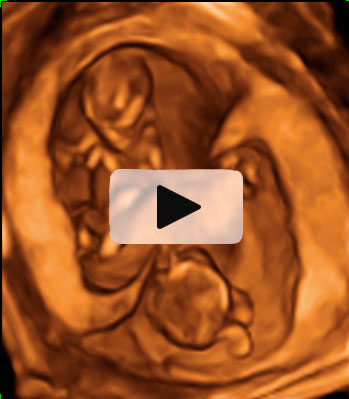

En la ecografía en 3D del feto en la 15ª semana de gestación se aprecia su anatomía. Es casi como la de un bebé a punto de nacer. Mide alrededor de los 10 cm y pesa unos 50 gramos.

Imagen de un feto de 15 semanas en ecografía 3D

La imagen es impresionante: la apariencia de este feto, de 15 semanas, es la de un niño que no le queda mucho tiempo de gestación para nacer. Cabeza, tronco, brazos y piernas se perfilan perfectamente en la ecografía del primer trimestre. Se lleva la mano a la boca mientras descansa apoyado en la pared uterina, como es normal es esta edad gestacional. La mayoría de las madres no se imagina que los fetos están tan "acabados" con apenas cuatro meses de embarazo.